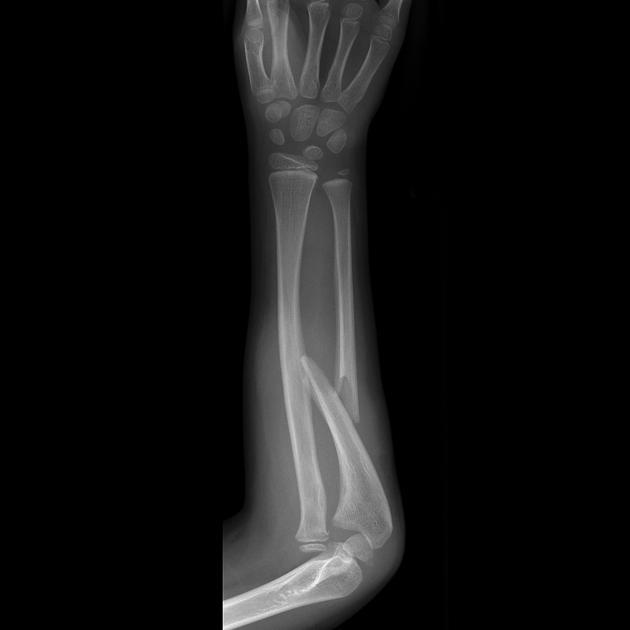

Diagnosis?

Monteggia fracture/dislocation - proximal ulnar fracture, radial dislocation (usually anterior). Due to fall on outstretched hand.